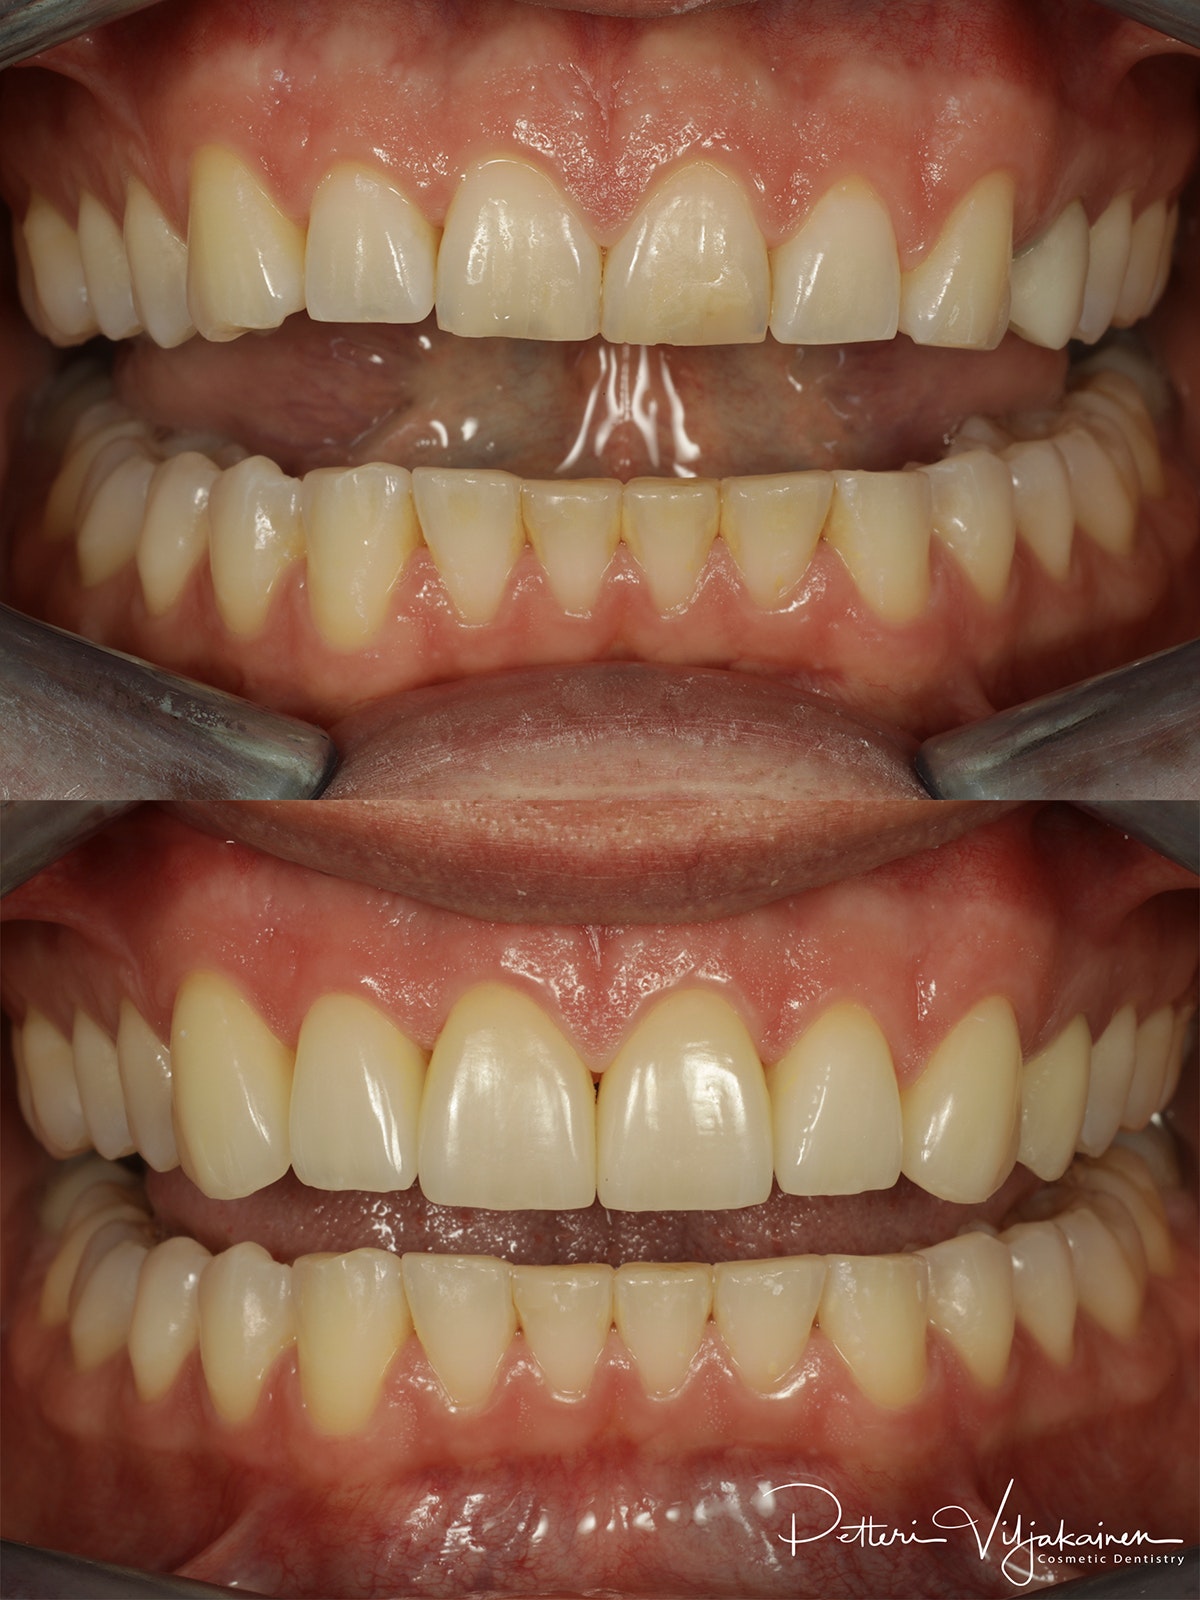

Keraamiset hammaslaminaatit seitsemässä yläetuhampaassa.

Keraamiset hammaslaminaatit kuudessa yläetuhampaassa.